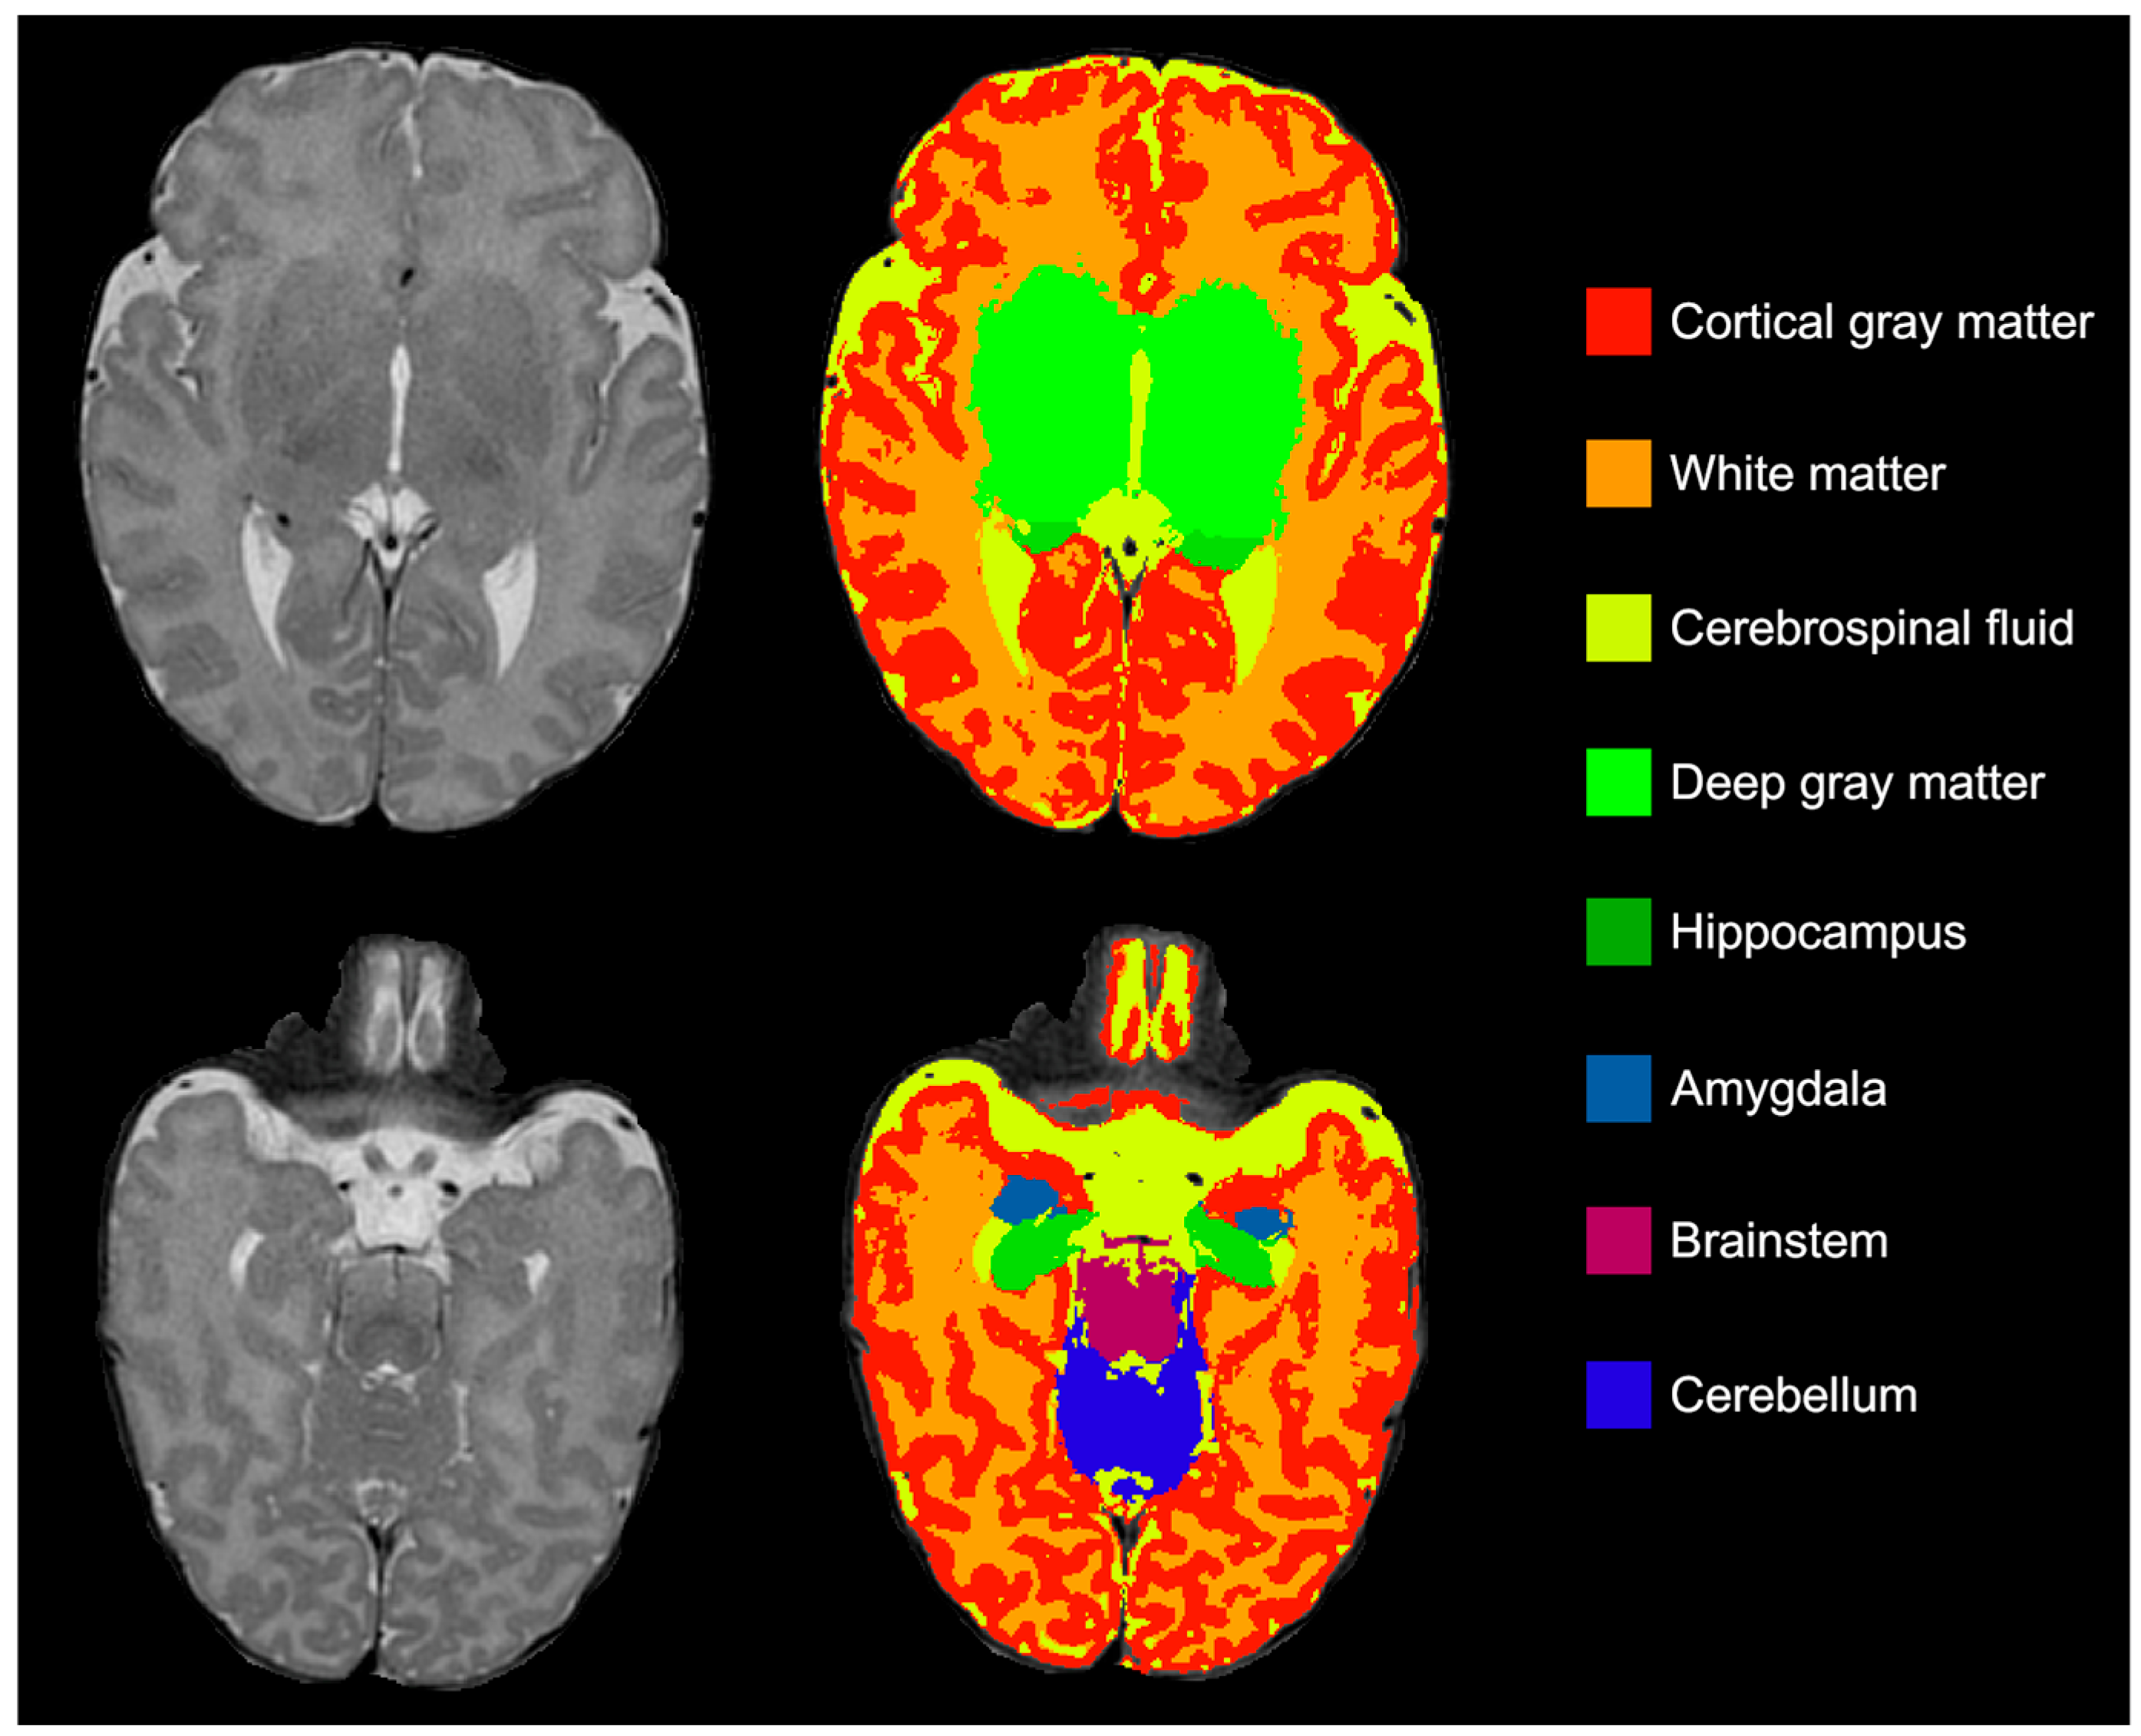

2.3. Brain Volumes

- Beare, R.J.; Chen, J.; Kelly, C.E.; Alexopoulos, D.; Smyser, C.D.; Rogers, C.E.; Loh, W.Y.; Matthews, L.G.; Cheong, J.L.Y.; Spittle, A.J.; et al. Neonatal Brain Tissue Classification with Morphological Adaptation and Unified Segmentation. Front. Neuroinform. 2016, 10, 143–155. [Google Scholar] [CrossRef]